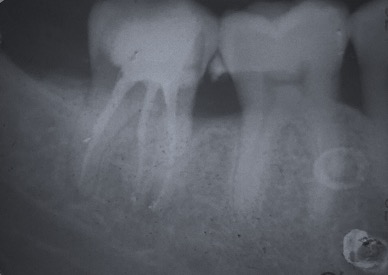

Capita spesso di incontrare denti già devitalizzati in maniera impropria che necessitano, seppur asintomatici, di essere ritrattati per evitare che i granulomi infetti visibili radiograficamente si evolvano riassorbendo tutto l’osso sottostante.

Un adeguata endondonzia serve per salvare quei denti che altrimenti sarebbero destinati ad essere estratti. Quando un dente viene devitalizzato viene privato della sua irrorazione sanguigna e del nutrimento, rendendo la sua struttura più “vetrosa” quindi più fragile e soggetta a fratture. Per questo motivo è consigliabile nella maggior parte dei casi capsulare i denti una volta che hanno perso la loro vitalità.